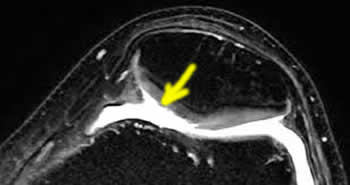

Le cartilage vu en IRM.

Ici le cartilage est normal en arthroscopie et sur l'IRM.

Images de chondropathies en IRM

Les chondropathies sont découvertes par le radiologue sur une IRM.